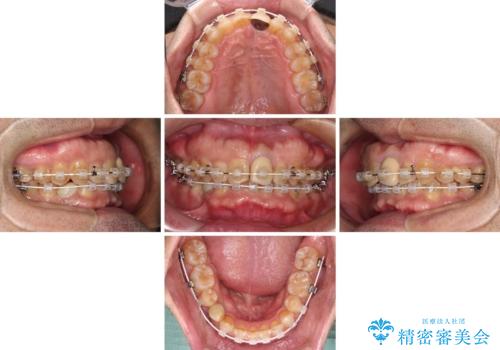

- 上下前歯のデコボコと下顎小臼歯の欠損によるスペースを気にして来院された患者様です。

下顎は左右1本ずつ小臼歯が欠損しており、右側にはやや大きな欠損がありました。

欠損により下顎歯列は相対的に小さく、上顎に深く咬みこんでしまうディープバイトとなっていました。

インビザラインによる治療を希望されたため、左側のスペースは閉じ、右側はスペースをより拡大し、インプラント補綴を行うこととしました。

咬合力が強く、インビザラインのみではディープバイトを改善することができず、半年間ほどワイヤー装置による矯正治療を行いました。

インプラントの埋入は矯正治療中に行い、矯正治療後はインプラント上補綴および、前歯のセラミック治療を行いました。